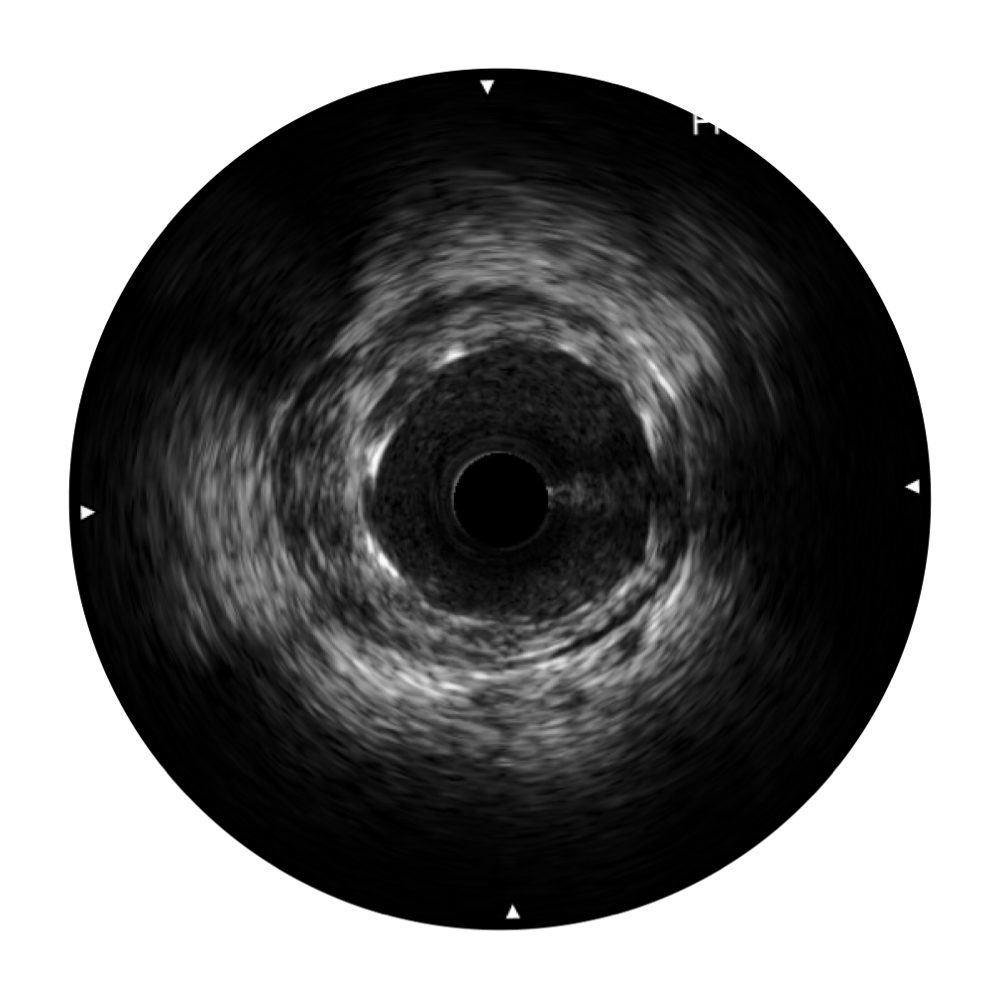

新葡的京集团8814检测站宽频IVUS图像

传统IVUS图像

对比传统IVUS导管成像,新葡的京集团8814检测站宽频IVUS图像的近场支架梁显影更细腻,远场中膜外血管仍清晰可辨,兼顾远中近,兼顾分辨力与穿透深度